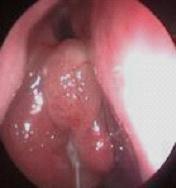

2、从鼻腔黏膜的病理学改变来分:慢性单纯性鼻炎、慢性肥厚性鼻炎、干酪性鼻炎、萎缩性鼻炎。此外,有一些慢性鼻炎,因有特定的致病原因、发病机制,因而便有特定的名称,如过敏性鼻炎、药物性鼻炎等。而鼻窦炎虽然也是鼻部的一个常见病和多发病,但因其特点突出,强调的是鼻窦发炎所致。

一、基本检查:1.前鼻镜检查。2.X线鼻泪管造影,明确有无并发鼻窦感染。